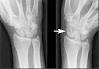

Bilder av hndleddsmerter Relaterte sprsml med samme svar: Hvorfor fr man smerter i hndledd?, Hva er rsak til hndledd smerter?, Ka er rsaka til ont i handleddene? HndleddHndFingre - Norsk Kiropraktorforening Hnleddsroten bestr av 8 forskjellige bein. Hei, i det siste n har jeg ftt smerter i hyre hndledd. Som nevnt i artikkelen vondt i hndleddet, s kan hndleddsmerter skyldes en rekke rsaker, blant annet.

Artroseforandringer, eller det vi p norsk kaller for slitasjegikt, er ikke uvanlig i dette omrdet. Hndleddet, senebetennelse - - Norsk Helseinformatikk outerHeight: 131 pageYOffset: 0 elementYOffset: 151 modifiedPageYOffset: 0.